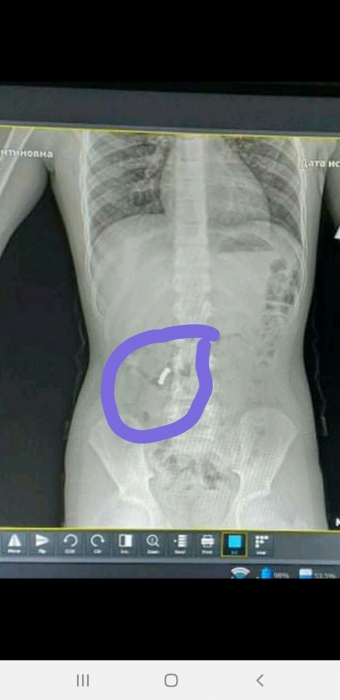

В Черноморске Одесской области школьник проглотил магниты. Они застряли в желудке ребенка и начали склеивать внутренние органы.

Четвероклассник проглотил одновременно четыре магнита. Для того, чтобы вытащить инородные предметы из мальчика, необходимо сделать дорогостоящую операцию с последующей реабилитацией.

"В нашей школе, в четвертом классе, произошла неприятная ситуация. Ребенок проглотил 4 магнитики, которые застряли в желудке и начали склеивать внутренние органы. Операция и реабилитация сложна и дорогостояща. Сейчас очень нужна материальная помощь родителям!", – сообщили на странице школы.